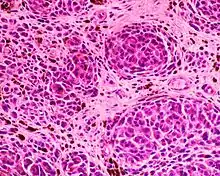

Epithelioid blue nevus Malignant blue nevus

Malignant blue nevus